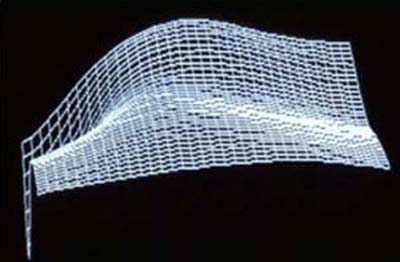

4 - TCC postop de Incisiones arqueadas

5 - Reconstrucción en Reja de alambre de Foto 4